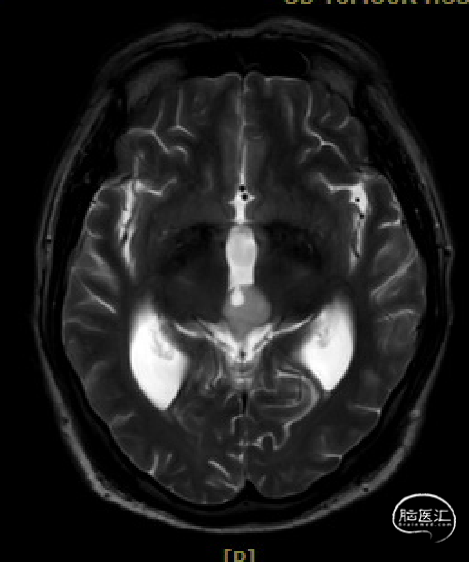

患者5年前无明显诱因出现阵发性头晕,无明显头痛、恶心呕吐等不适,开始未予重视,2022-7-19出现头晕加重,伴视力下降,遂于2022-7-24在当地医院行颅脑MRI提示:松果体区肿瘤伴梗阻性脑积水。

于该院在2022-7-27全麻下行松果体区病灶部分切除活检+神经内镜下第三脑室底造瘘术,术后由于取出肿瘤组织少,未能明确病理结果。患者术后恢复顺利,为进一步治疗就诊于我院。

入院检查

松果体区占位,胶质瘤?生殖细胞肿瘤?

脑积水

脑梗死